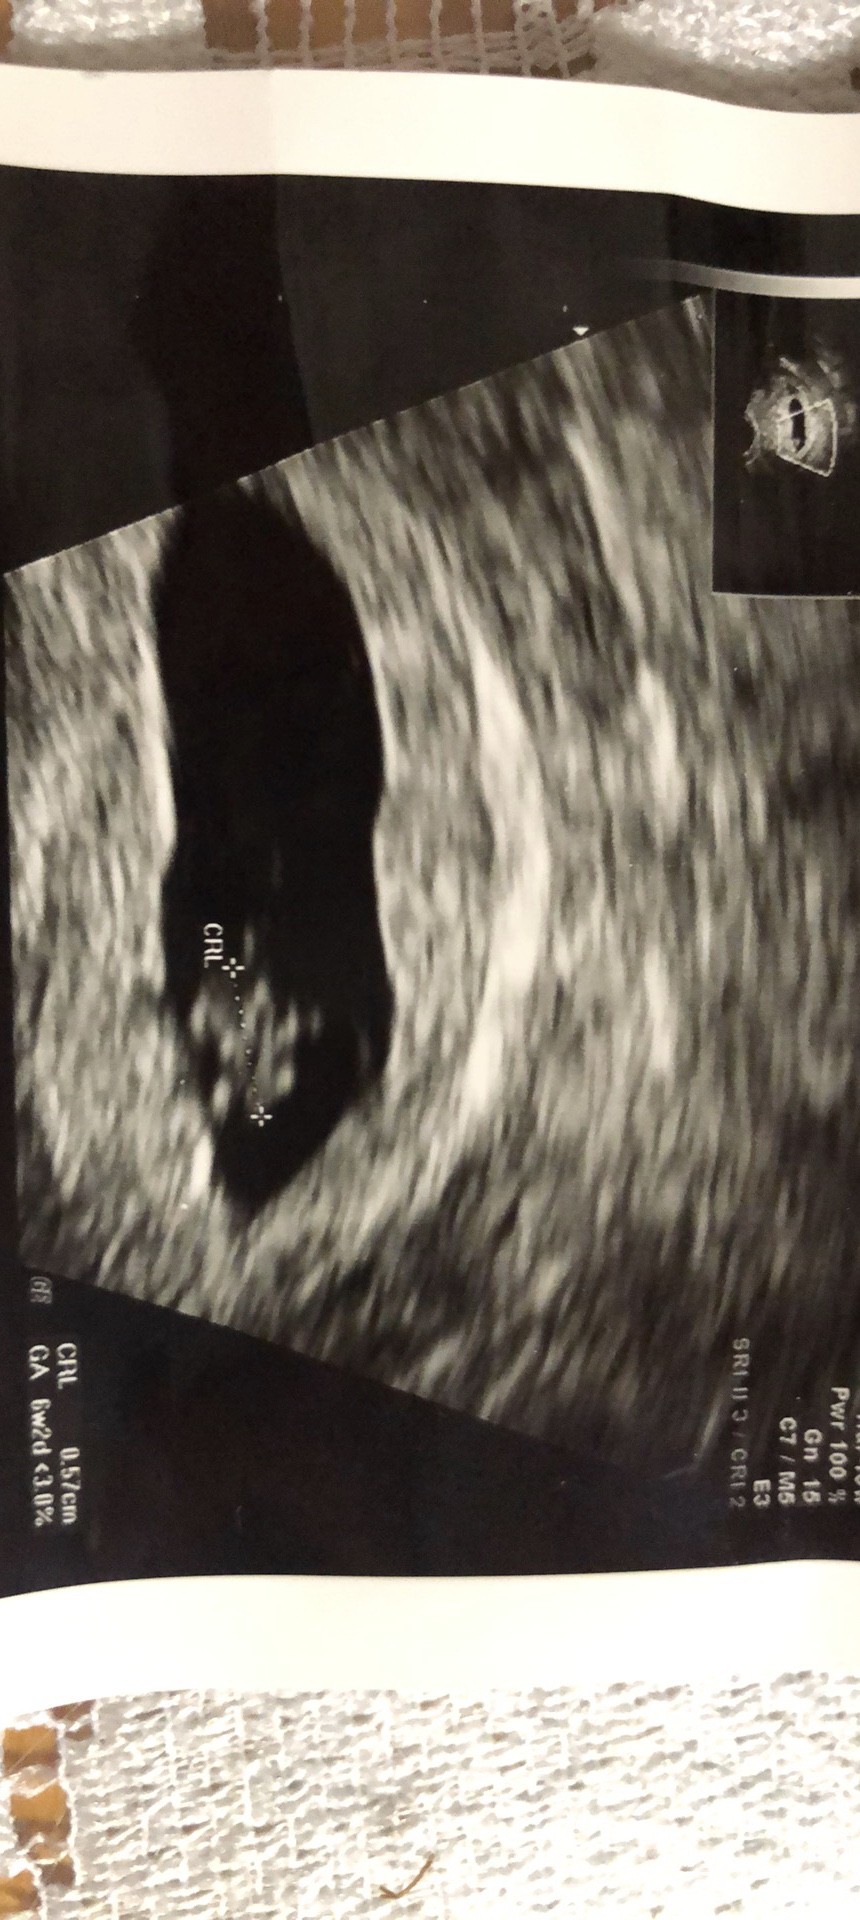

jestem zawsze tak zestresowana że po wejściu do gabinetu wyłącza mi się myślenie. Zapominam zapytać o połowę rzeczy, nie dopytuje tylko przytakuje... I tym sposobem na ostatniej wizycie ginekolog stwierdził że moja macica ma jakieś zwężenie

nie jestem pewna ale coś mówił o jej kształcie. I teraz nie pamiętam czy mówił że to może utrudniać zajście czy donoszenie

boje sie że to macica dwurozna

tak jak pisałam na poczatku- w poniedziałek zadzwonię i dopytam co i jak ale jakoś nie daje mi to spokoju. W czerwcu poronilam w 8tyg, serduszko przestalo bić. W lutym chcemy wznowić starania a tu ciągle jakieś dodatkowe stresy